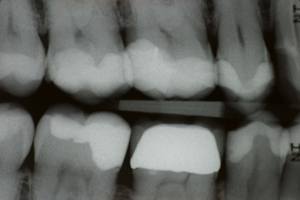

Voor een posterieure restauratie kan gekozen worden uit een directe of indirecte techniek. Voor directe restauraties heeft het composiet het amalgaam definitief verdrongen, voor indirecte restauraties wisselen de vernieuwingen qua materialen elkaar in snel tempo af. Traditioneel heeft de indirecte restauratie de reputatie een langere levensduur te hebben maar de adhesieve tandheelkunde heeft ervoor gezorgd dat composieten posterieur een goede levensduur kunnen bereiken. Het streven naar metaalvrij werken voor kronen, bruggen en inlays heeft het fractuurrisico wat vergroot.

Vanuit de laatste stand der wetenschap zal Niek Opdam een overzicht geven wat er qua levensduur verwacht kan worden van verschillende restauratietypen, zowel vanuit de gegevens van klinische universiteitsstudies als het werk van de Nederlandse tandarts. Daarbij komt steeds meer naar voren dat materiaaleigenschappen en details van de techniek ondergeschikt zijn aan patiëntgebonden factoren.

Composiet wordt wereldwijd beschouwd als eerste keuze materiaal voor directe restauraties in de posterieure regio. De levensduur van de posterieure composietrestauratie is gunstig. Verschillende reviews noteren een jaarlijks faalpercentage van 1-3%. Een correct uitgevoerde klinische procedure speelt een kritische rol m.b.t de levensduur van de posterieure composietrestauratie.